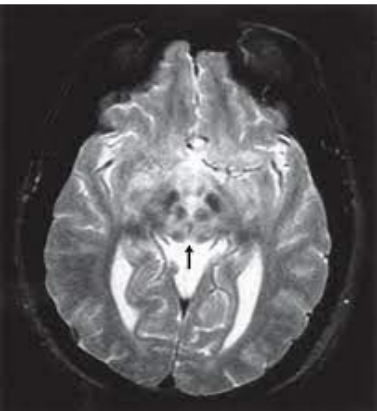

Considere a figura a seguir, que apresenta uma imagem de ressonância nuclear magnética (RNM) com alteração típica no encéfalo, para responder a esta questão.

SONAM, K.; BINDU, P.S.; GAYATHRI N. et al. The “double panda” sign in Leigh disease. Journal of Child Neurology. 2014, v. 29, n. 7, p. 980-982.

Analise as afirmativas sobre a RNM.

I. O diagnóstico da doença de Wilson não pode baseado apenas nesta imagem.

PORQUE

II. O sinal do panda gigante pode estar presente na sarcoidose e síndrome de Leight.

Assinale a alternativa CORRETA.